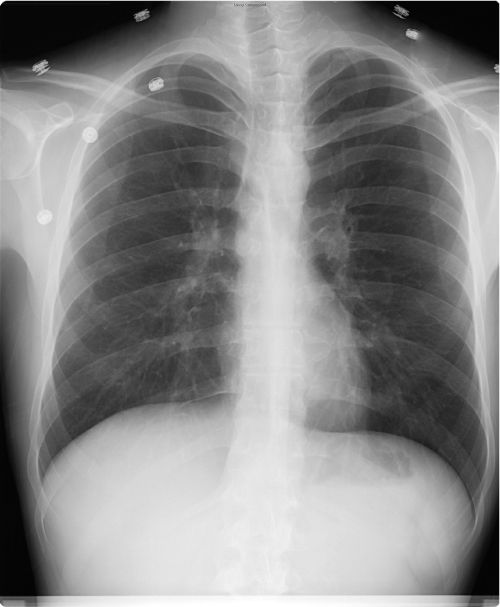

From pubs.rsna.org

Imaging of the Diaphragm Anatomy and Function RadioGraphics Loss Of Diaphragm Function Diaphragm dysfunction is characterized by diminished contractile function of the diaphragm muscle, presenting as muscular weakness, partial. Most of the time, the diaphragm moves involuntarily. This can result from muscular. The diaphragm plays an integral role in respiration (breathing). Diaphragmatic dysfunction is an underdiagnosed cause of dyspnea and should always be considered in the differential diagnosis of unexplained dyspnea. Unilateral. Loss Of Diaphragm Function.